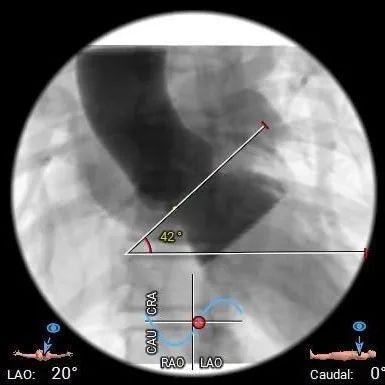

三叶式主动脉瓣,瓣叶增厚,水平夹角42°;LVOT微微敞口

• 拟主动脉瓣水平夹角约42°,非横位心,主动脉弓宽度角度可